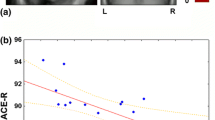

Using ASL-MRI, PLD1.5 scans revealed significant positive correlations with MMSE results in the right posterior cingulate cortex (PCC) and both temporo-parietal association cortexes, in addition to the right rectal gyrus (Fig 1a). PLD2.5 showed significant positive correlations in the superior parietal lobule but not PCC, and the right temporo-parietal association cortex only. Positive correlations for the right inferior temporal lobule and right fusiform gyrus were also significant (Fig 2a). Brain perfusion SPECT identified significant positive correlations in the PCC and both temporo-parietal association cortexes (right-side dominant), and the left fusiform gyrus (Fig 3a). The plots of the correlation between the voxel values and MMSE scores at the most significant area are shown in Figs. 1b, 2b, and 3b. All of them showed linear relationships. The expected voxels per cluster for PLD1.5, PLD2.5, and SPECT were 63.4, 40.8, and 60.9, respectively. Cluster-level statistics for all rendered clusters are summarized in Table 2.

From the results of our study, we identified significant positive correlations between CBF and cognition, when measuring using both ASL-MRI and SPECT. The main areas with significant results were located in PCC and temporo-parietal association cortexes, which are known to show decreases in perfusion or metabolism during cognitive decline in association with AD [25,26,27,28]. These areas are the posterior parts of the default mode network (DMN), which has a primary network center in the PCC. These regions have a strong functional connection to the left and right inferior parietal lobule (IPL), ventral and dorsal medial prefrontal cortex, and lateral temporal lobes [29]. Functional MRI studies have also consistently implicated the DMN as the most vulnerable network in AD [30, 31]. The posterior (temporo-parietal-predominant) DMN may be particularly susceptible in early-stage AD [32–34]. These studies therefore support our findings that a significant correlation exists between CBF and cognition, in the PCC and IPL. To the best of our knowledge, ours is the first report that succeeded in demonstrating such correlations between CBF and cognition using ASL-MRI, with supporting data using SPECT. These correlations may support the idea that regional CBF can serve as a biomarker of the neural changes underlying cognitive decline. As shown in Figs. 1b and 2b, the voxel values of SPM results dropped linearly with decreasing MMSE scores. Our results also showed similar significant correlations between cognition and CBF using ASL-MRI with PLD1.5 and PLD2.5, and SPECT. The measurement of CBF is thought to be influenced by modalities, tracers, and parameters. In fact, our results showed that ASL-MRI with PLD1.5 and PLD2.5 have significant differences. A significantly higher CBF was found at the adjacent areas of anterior cerebral arteries, middle cerebral arteries and posterior cerebral arteries for PLD1.5 compared to PLD2.5, suggesting early perfused areas. Liu et al. [35] evaluated the CBF of AD patients using ASL-MRI with PLD1.5 and PLD2.5, and identified lower CBF for both PLD durations at the specific area of AD pathology when compared to healthy control subjects, but with smaller clusters of voxel for PLD2.5. Despite of these significant differences in measured CBF using ASL-MRI with PLD1.5 and PLD2.5, PCC and temporo-parietal association cortexes were detected with significant correlations with cognition. This may suggest a possibility of the usefulness for the individual diagnosis using voxel-wise analyses of ASL-MRI. In Japan, voxel-wise analyses of SPECT using 3-Dimensional stereotactic surface projections (3D–SSP) [36] and an SPM-based method termed “easy Z-score imaging system (eZIS)” [37, 38] have been commonly used for the individual diagnoses in daily practices. Such voxel-wise methods may be helpful for making individual diagnoses using ASL-MRI. However, an age-specific normal database is required for the detection of significant abnormalities of individual images.

Our results also demonstrate a significant correlation between CBF and cognition at the right rectal gyrus for PLD1.5, and the right inferior temporal lobule and fusiform gyrus for PLD2.5. However, these areas are located at the edge of the brain, and these results might be caused by the errors during anatomical standardization and/or masking, and seem to be artifacts.